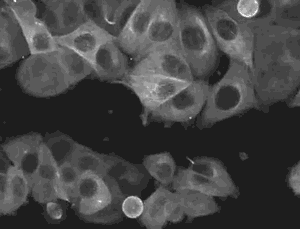

8上皮细胞有丝分裂

有丝分裂是细胞核分裂的过程.通过有丝分裂,每条染色体精确复制成的两条染色单体均等地分到两个子细胞,使子细胞含有同母细胞相同的遗传信息。